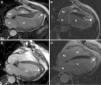

Material y métodosRevisamos retrospectivamente 21 pacientes consecutivos con miocardiopatía dilatada isquémica sometidos a endoventriculoplastia entre enero de 2007 y marzo de 2013. En 12 de ellos se realizó RMC pre- y posquirúrgica. En las RMC diagnóstica y posquirúrgica se hizo un análisis cuantitativo de la fracción de eyección (FEVI), volúmenes telediastólico (VTDVI) y telesistólico (VTSVI) del ventrículo izquierdo indexados, y se valoraron las valvulopatías y trombos intracavitarios. El tiempo transcurrido entre la intervención quirúrgica y los estudios de control con RMC osciló entre 3 y 24 meses.

Material and methodsData were retrospectively gathered on 21 patients with diagnosis of ventricular aneurysm secondary to ischemic heart disease undergoing left endoventriculoplasty repair between January 2007 and March 2013. Pre and post-operative CMR was performed in 12 patients. The following data were evaluated in pre-operative and post-operative CMR studies: quantitative analysis of left ventricular ejection fraction (LVEF), left ventricular end-diastolic (LVEDV) and end-systolic (LVESV) volume index, presence of valvular disease and intracardiac thrombi. The time between surgery and post-operative CRM studies was 3–24 months.